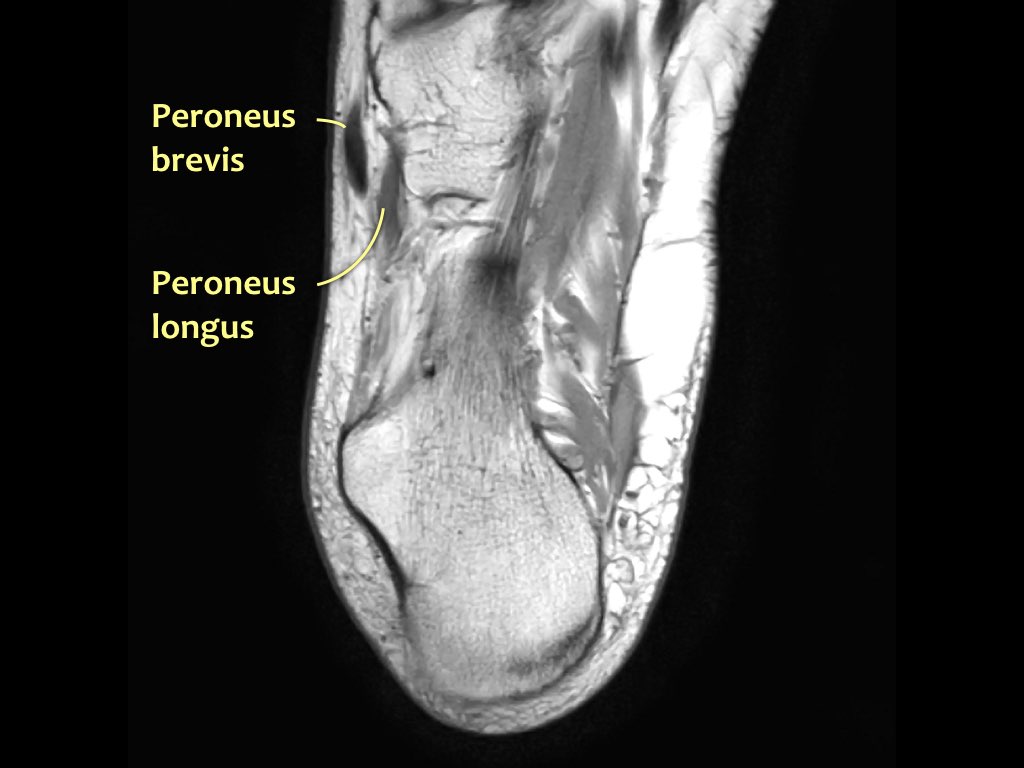

- Khoang ngoài

- Gân cơ mác dài (Peroneus Longus)

- Gân cơ mác ngắn (Peroneus Brevis)